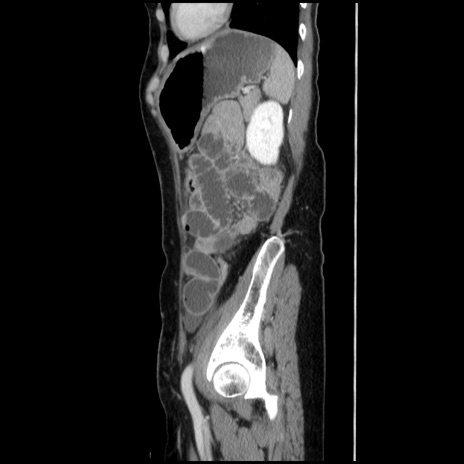

症例32(矢状断像)

【症例】40歳代 女性

【主訴】上腹部痛、嘔気・嘔吐

【現病歴】約9時間前頃から急に上腹部痛、嘔気、嘔吐が出現。改善しないため救急要請。

【既往歴】子宮頚癌(広汎子宮全摘術、放射線療法)、腸閉塞

【身体所見】腹部:平坦、軟、腸雑音亢進、上腹部を中心に腹部全体に圧痛あり。

【データ】WBC 8400、CRP 0.03